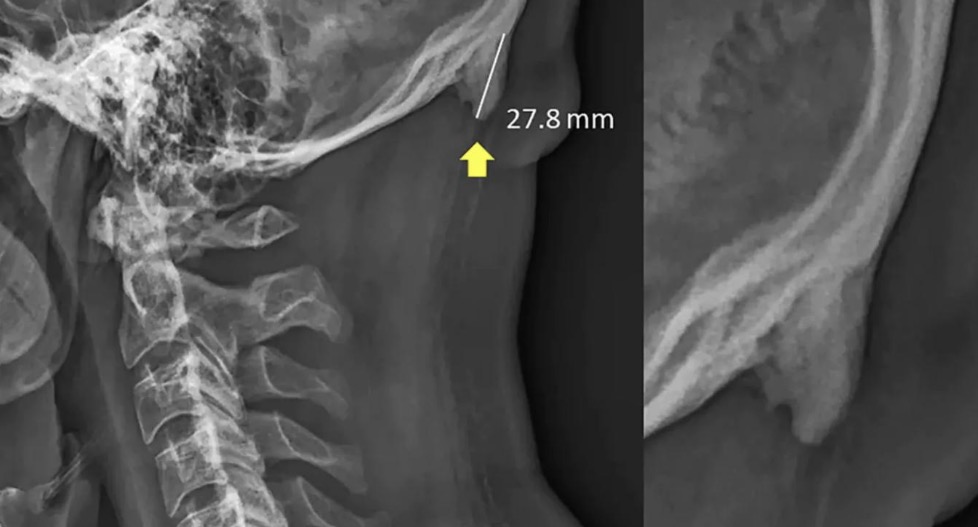

The 'Texting Horns' Theory meme stems from a 2016 scientific study that gained massive media attention in 2019, suggesting that young adults were developing 'external occipital protuberances'—essentially bone spurs—due to the forward tilt of the head while using smartphones. While the scientific validity of the 'horns' being caused solely by phones was heavily debated by experts, the internet immediately turned the concept into a viral sensation. The meme typically features an X-ray of a skull with a pointed protrusion at the base, used to joke about the physical evolution of Gen Z or to satirize sensationalist health news. It serves as a humorous commentary on modern technology's perceived impact on human anatomy and the often-alarmist nature of digital-age health reports.